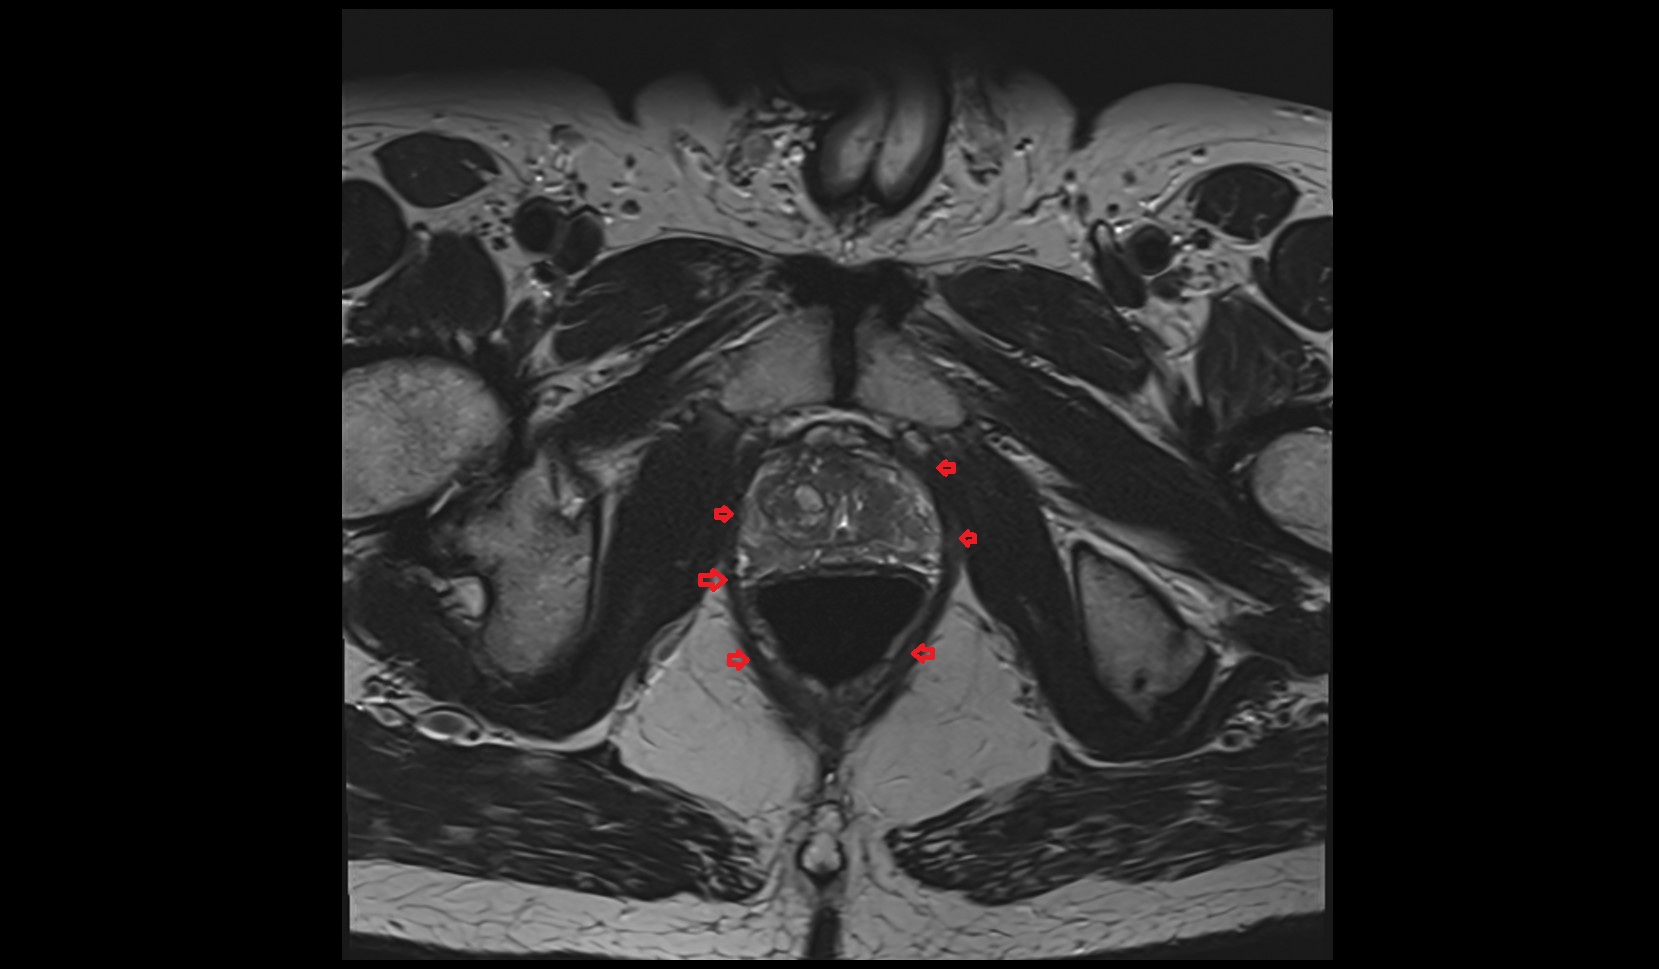

- Peripheral zone of prostate

- Anterior Fibromuscular Stroma of prostate

- Central zone of prostate

- Transitional zone of prostate